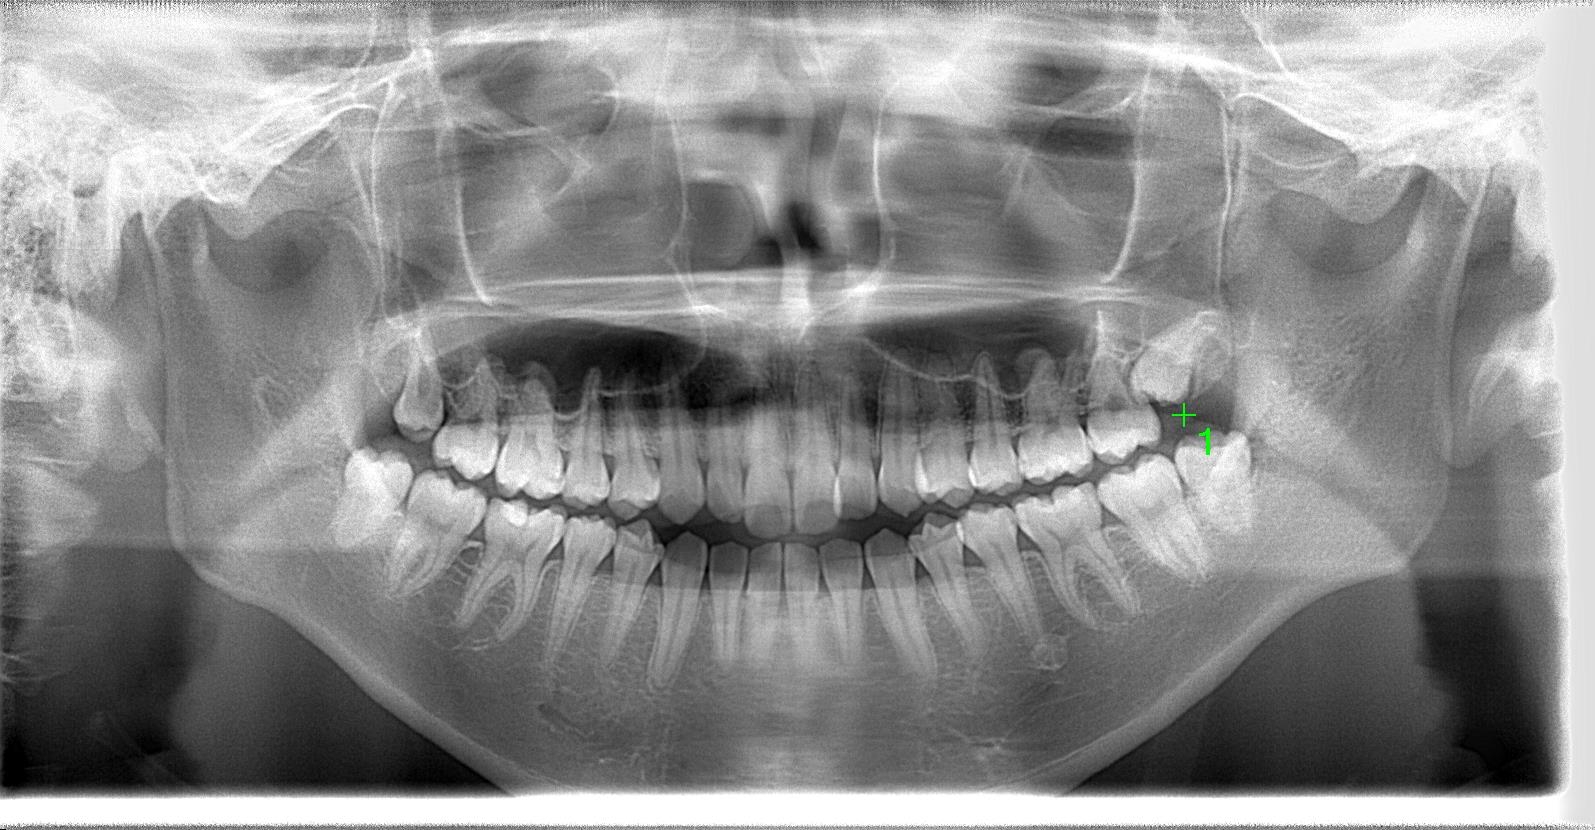

術前のパノラマレントゲン写真

術前

部位:左上8番骨性完全埋伏歯

部位:左下8番埋伏歯